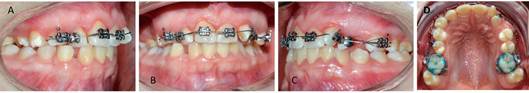

La planificación del tratamiento de Ortodoncia comprendió un tratamiento bimaxilar de compromiso con exodoncias de los dientes 1.3 - 6.3 y 8.3. El plan de tratamiento inicial comenzó con el uso de aparatología Multibrackets MBT .022 con bandas en molares superiores e inferiores. La paciente no consentía sesiones de más de 15 minutos, realizando la instalación parcial superior, a modo de adaptación al tratamiento de ortodoncia, para posteriormente continuar con instalación de arcada inferior. Se derivó a Odontopediatría para las exodoncias de los dientes 1.3 - 6.3 y 8.3. Luego de cuatro meses, la cuidadora refiere que la paciente descementaba intencionalmente los brackets con un lápiz. Si bien se realizó la reposición de éstos, el mal hábito persistió, por lo que se adoptó como alternativa de tratamiento instalar botones, con el objetivo de generar cupla y desrotar los incisivos superiores, continuando con la etapa de alineación y nivelación (figura 4). El mal comportamiento de la paciente persistió en el tiempo, pero aun cuando tenía indicación de retiro de los aparatos, debido a su conducta y la permanente gingivitis, se determinó modificar los objetivos terapéuticos propuestos en un inicio del tratamiento, dando prioridad a lograr el cierre del espacio provocado por la exodoncia del diente 6.3 para la alineación de la arcada superior. Por ellos, se suspendió la instalación de brackets en la arcada inferior y se decidió confeccionar bandas individuales para los dientes que requerían mayor alineación, utilizando como secuencia de arco un Niti Natural .014 y .020, junto con un SS .020 (Figura 5)